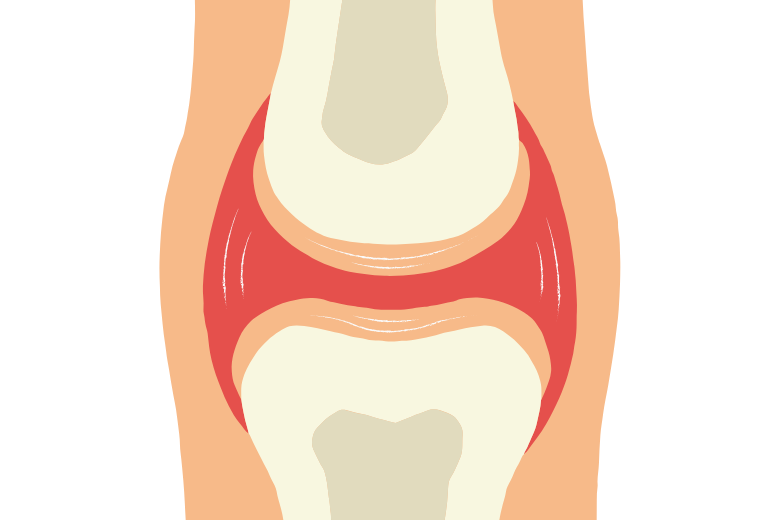

この時、中央と端の境目にあたる部分には、まだ軟骨が残されています。ここを 骨端線(成長軟骨帯) と呼びます。子どもの骨のX線写真を見ると、骨の両端にスジのように見える部分があり、それがまさに成長軟骨帯です。

成長軟骨帯は、骨の成長にとって極めて重要な場所です。この部分の軟骨は子どもの間は残り続け、ここで軟骨が新しく作られ、それが骨に置き換わることで、骨が縦方向に伸びていきます。

イメージとしては、「軟骨が前へ進むと、その後を追うように骨が作られる」仕組みです。例えるなら、馬の前にぶら下げられたニンジンを追いかけるように、軟骨が伸びると骨がその分だけ追いつき、結果として骨の長さが伸びていくのです。

この仕組みのおかげで、子どもは小学生から中学生の時期にかけて急速に身長が伸びることになります。そして、思春期の終わり頃、成長軟骨帯は完全に骨へと置き換わり、閉じてしまいます。これを「骨端線が閉じる」と表現し、身長の伸びが止まる大きな節目となります。